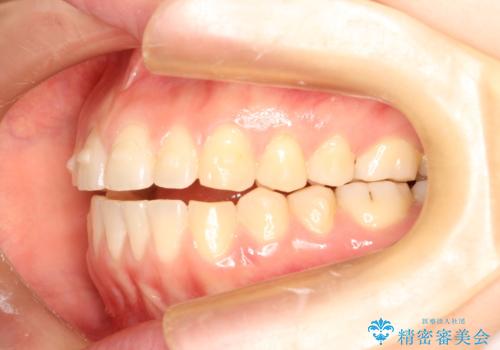

上下の前歯が当たらない インビザラインによる開咬の矯正治療

- 上下の前歯の間に隙間があるとのことで来院されました。

開咬とよばれる、奥歯しか上下の歯が接触していない状態でした。

インビザラインにて矯正治療を行うこととなりました。

使用時間を守っていただけたので、比較的スムーズに矯正を終了することができました。

前歯で物が咬み切れるようになり、喜んでいただけました。

舌の使い方が上手ではなかったので、治療と同時に舌のトレーニングを行いました。

舌の使い方も矯正治療と非常に関係があります。